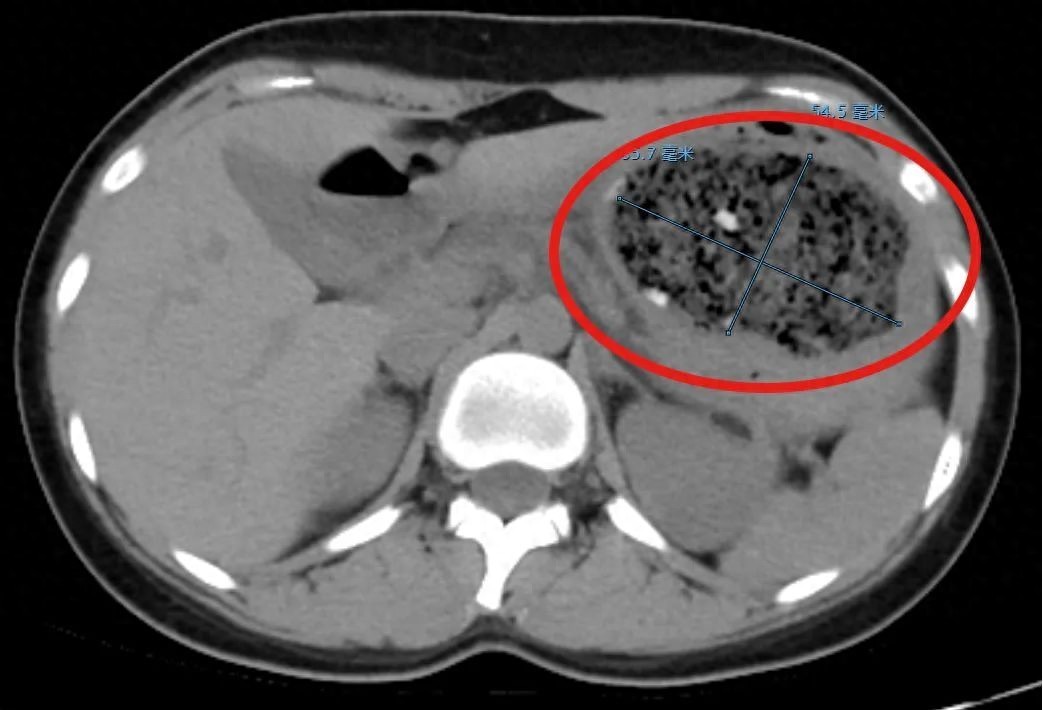

来源:杭州日报19岁大二学生倩倩(化名)是糖炒山楂的忠实爱好者。这种酸酸涩涩的味道很上头,每年山楂一上市,她必定会买来解馋。但最近,她偏偏就被这酸甜开胃的山楂整进了医院。1斤多山楂下肚,巨大“石头”塞满整个胃医生:多喝可乐近日,倩倩买了1斤多糖霜小山楂来吃,结果当天晚上就感到肚子痛。起初还勉强能忍受,可到了第二天,腹痛却越来越严重,疼得她直打滚,最后来到了杭州市第一人民医院门诊。接诊的消化内科副主任杨晶简单问了病史后,给倩倩安排了腹部CT平扫检查,结果发现一个8.6cm×5.5cm左右的巨大的异物把她的胃塞得满满当当!

图片来源于稿源单位“你吃了多少山楂?”杨晶问。“一个人吃了1斤多,大概有30多颗……”倩倩怯怯地说。经验丰富的杨晶立刻做了明确诊断——胃石。在进一步胃镜检查后,杨晶发现,倩倩胃里面的结石体积庞大,几乎不留什么空隙,这使得常规的异物圈套器无法施展。为此,杨晶决定先用工具将结石分割成小块,但由于结石太多,如果直接一一取出,会对喉咙造成损伤,他选择让这些小块结石留在里面,并再三嘱咐倩倩,这几天多喝可乐。根据医嘱,倩倩喝了两天的可乐,果然,四天后复查,检查结果显示,她胃内的结石已完全溶解消失。不只是柿子!很多食物都会引发结石“只听说柿子吃多了会得柿石,怎么山楂也会引发结石?”倩倩百思不得其解。杨晶解释,胃石并非仅限于“柿石”,其实只要富含“鞣酸”的食物,如香蕉、山楂等,在特定条件下同样可能形成结石,需引起高度警惕。为什么可乐能消除结石呢?杨晶解释,这是因为可口可乐含有大量二氧化碳,会产生膨胀效应,而磷酸、柠檬酸和碳酸氢钠,也会和结石中的钙等物质产生化学反应,破坏结石聚合,达到溶石的目的。但注意,有胃石特别是合并溃疡症状的患者,不能盲目饮用可乐。因为可乐可能会造成溃疡的进一步加重,要在专业医生的指导下进行,并建议尽早去医院进行综合治疗。注意健康饮食不必“谈石色变”“今年门诊已经收到好几例类似的病例,每年到柿子、山楂上市的季节,更是高发。不过,不用过于恐慌,任何事情都不能‘抛开剂量讲毒性’。产生胃结石的前提是大量食用。”杨医生说。因为“胃石”住院虽然惊险,但大多数预后良好。“只要有正确的饮食观念,在满足我们的口福同时,不必谈石色变。”杨医生发出以下提醒,吃货们请收好:选择成熟的柿子或山楂等食物。注意摄入量,不可贪吃。避免高蛋白食物共同食用。消化功能差的人群要减少摄入,如老人、儿童要特别注意。进食后注意口腔清洁,避免鞣酸对牙齿造成损伤。如有不适及时入院就诊,千万不可听信偏方治疗。来源:健康杭州